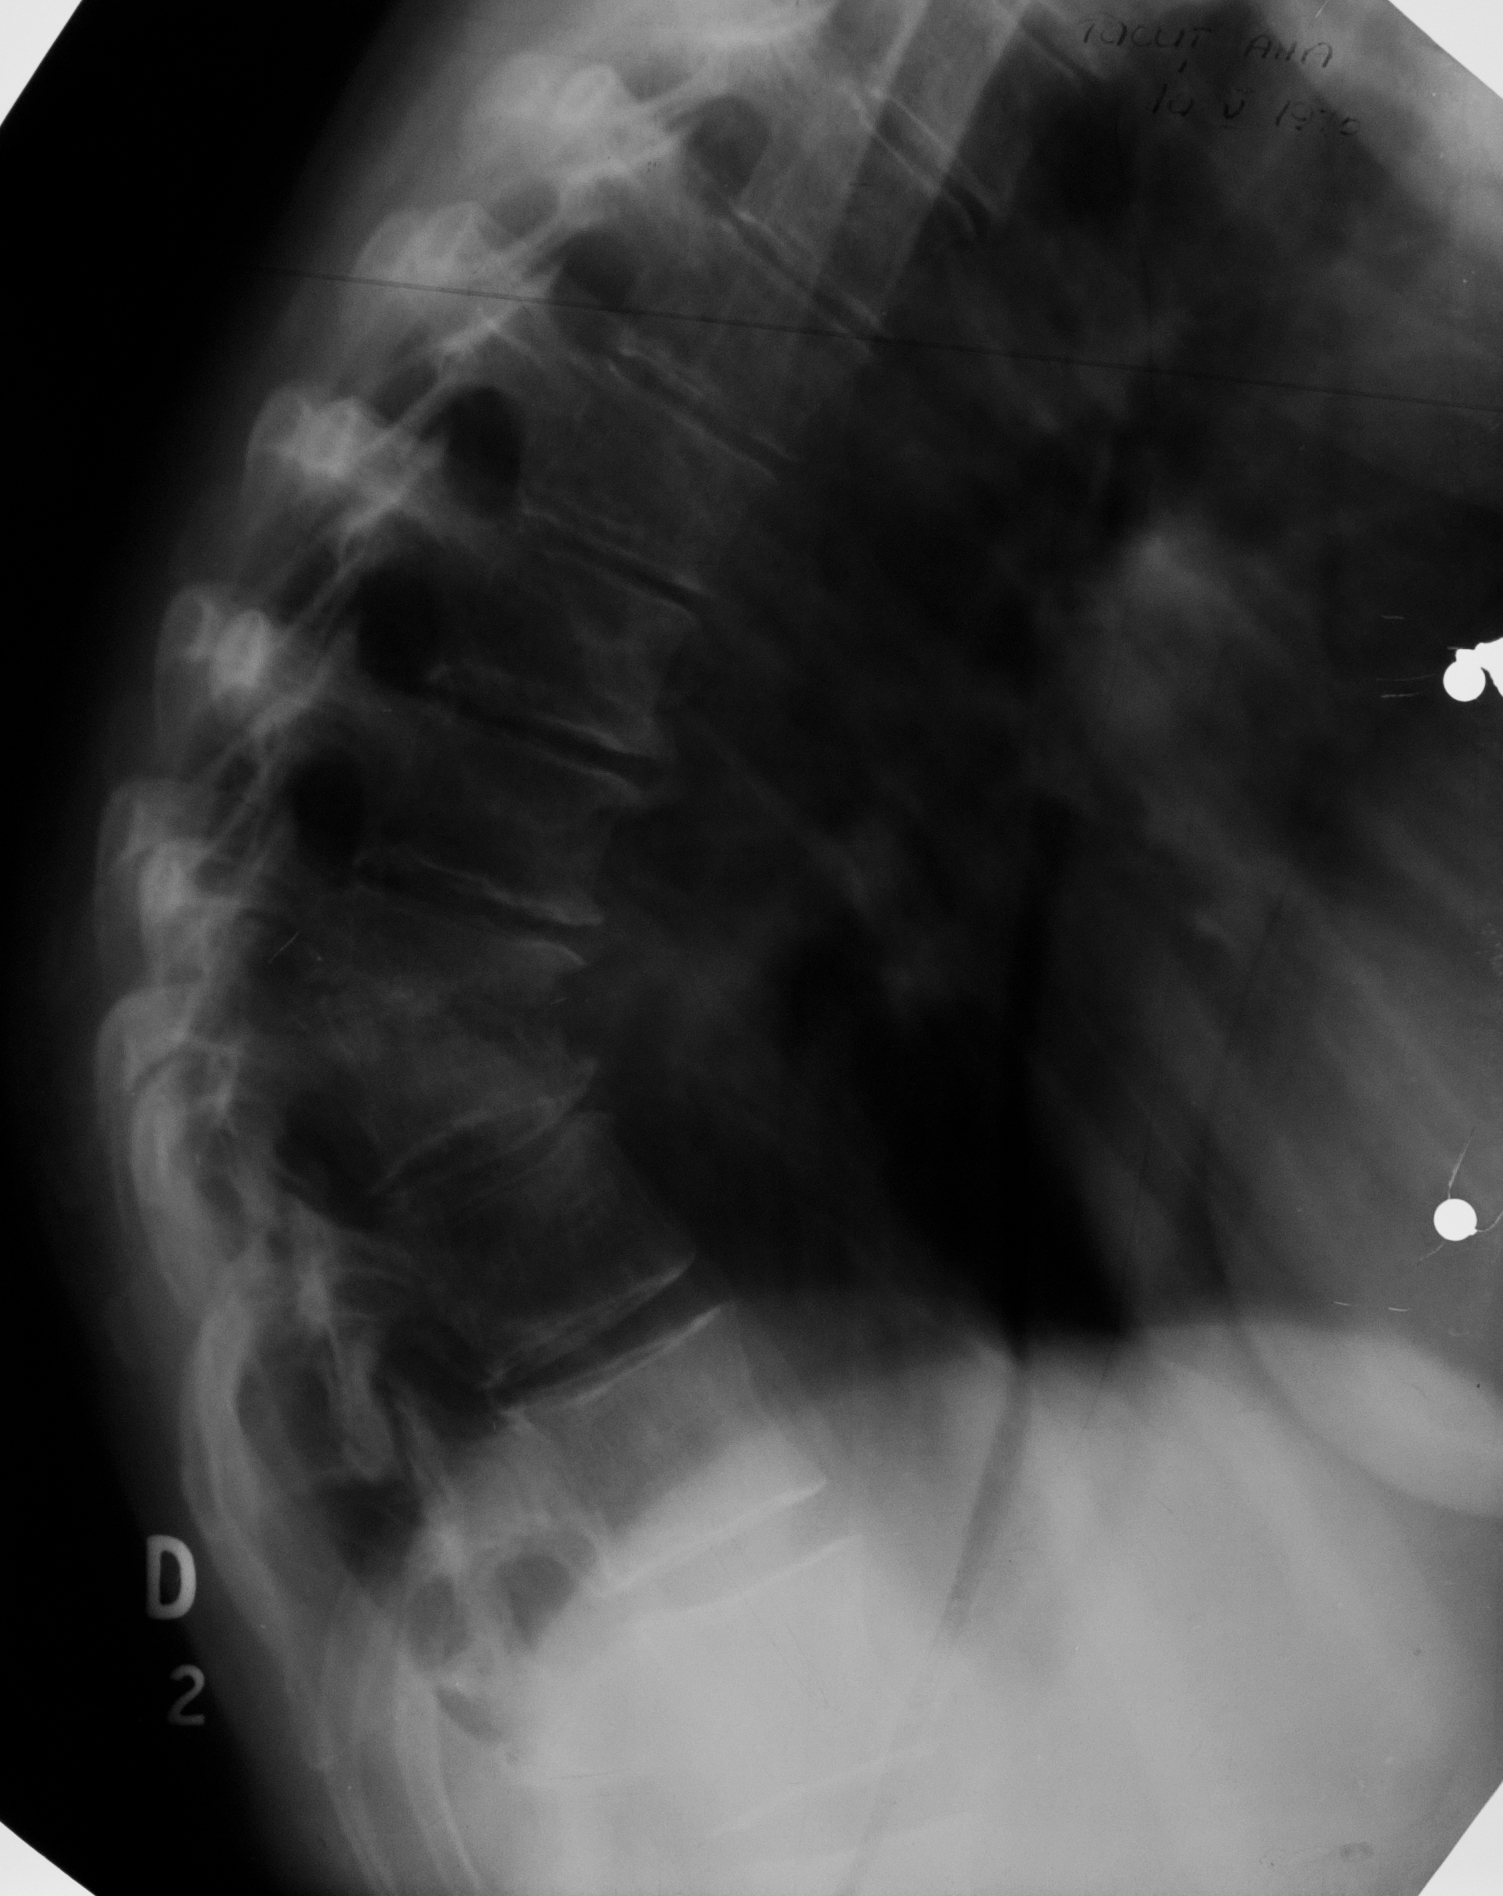

Osteoartrita TBC la nivelul coloanei vertebrale

Radiografie de coloana toracala, se vad 2 corpuri vertebrale cu spatial dintre ele absent, ele de dimensiuni mai reduse decat normal cu suprafete articulare neregulate, iar adiacent opacitate fusiforma

!!! Se cheama: Morbul lui Bot, (umflatura de pe margine e fusul Botic)

OSTEOARTRITĂ TBC

Accentuarea cifozei dorsale, nu e rotunda ci unghiulara, datorata distructiei unor corpuri vertebrale (lizei acestora), ramanând niste resturi care s-au sudat partial si au facut un bloc vertebral botic

CIFOZĂ ÎN URMA TUBERCULOZEI VERTEBRALE